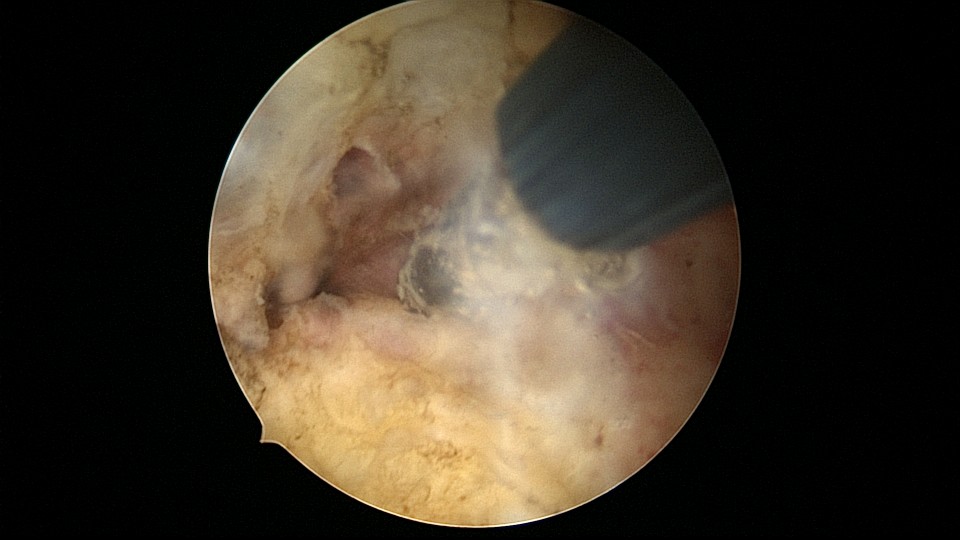

患者56岁,G2P1,顺产1次。安环16年,绝经1年,外院取环失败。宫颈外口及宫颈内口狭小质硬,分别用中弯钳及异物钳扩张,宫腔镜见宫颈管息肉2个,宫型环与宫壁嵌顿,异物钳取出,单级电针切除息肉送病检,病检结果为宫颈管息肉,宫腔未见其他异常。